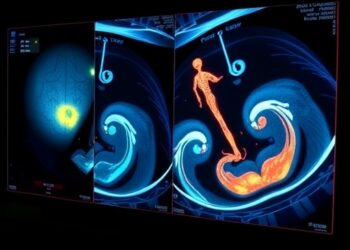

Real-Time 3D Ultrasound Boosts AR Training Success

In a remarkable leap forward for medical training and surgical precision, researchers have unveiled a cutting-edge system that integrates real-time...